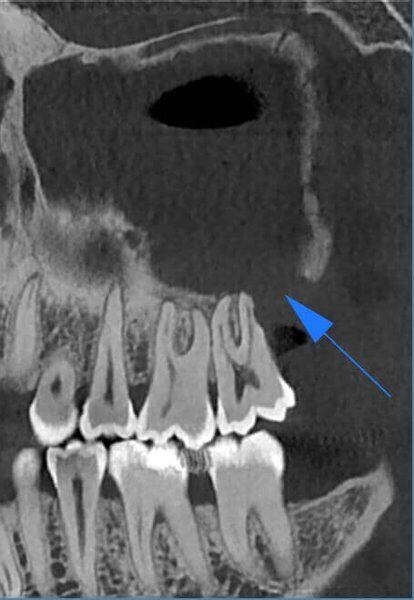

Rottura del pavimento del Seno Mascellare sinistro con Sinusite